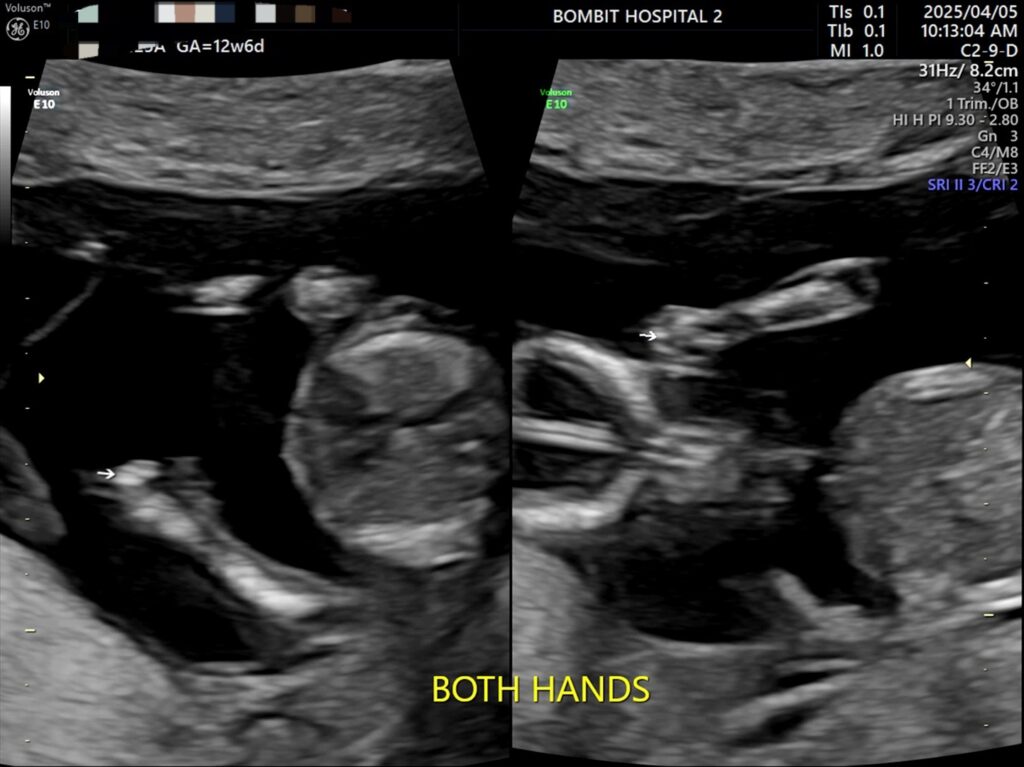

봄빛병원에 다시 방문. 정밀초음파도 하고, 다시 진료도 보았다.

피고임은 이제 없어졌다고 했다. 약간은 느려진 듯한 심장소리도 다시 들었고 니프티 검사용 채혈도 했다.

정밀초음파 사진.